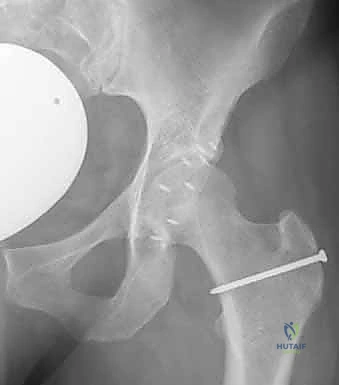

- التصوير بالأشعة السينية (X-rays): صور دقيقة بوضعيات خاصة (AP Pelvis, Dunn view, Cross-table lateral) لقياس زوايا محددة مثل زاوية ألفا (Alpha Angle) التي تؤكد وجود تشوه "كام"، وعلامة التقاطع (Crossover Sign) التي تؤكد وجود تشوه "بنسر".

صورة شعاعية قبل التدخل الجراحي توضح التشوه العظمي بوضوح.